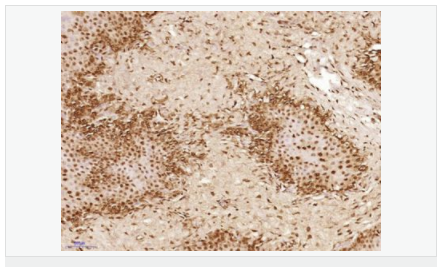

交叉反應(yīng):Human,Mouse,Rat(predicted:Dog,Pig,Cow,Horse,Rabbit,Sheep) 推薦應(yīng)用:IHC-P,IHC-F,ICC,IF

交叉反應(yīng):Human,Mouse,Rat(predicted:Dog,Pig,Cow,Horse,Rabbit,Sheep) 推薦應(yīng)用:IHC-P,IHC-F,ICC,IF

| 產(chǎn)品應(yīng)用 | IHC-P=1:100-500 IHC-F=1:100-500 ICC=1:100-500 IF=1:100-500 (石蠟切片需做抗原修復(fù)) not yet tested in other applications. optimal dilutions/concentrations should be determined by the end user. |

| 細(xì)胞定位 | 細(xì)胞核 細(xì)胞漿 |

| 產(chǎn)品介紹 | This gene encodes a member of the TET family of RNA-binding proteins. The encoded protein plays a role in RNA polymerase II gene transcription as a component of a distinct subset of multi-subunit transcription initiation factor TFIID complexes. Translocations involving this gene play a role in acute leukemia and extraskeletal myxoid chondrosarcoma, and mutations in this gene may play a role in amyotrophic lateral sclerosis. Alternatively spliced transcript variants encoding multiple isoforms have been observed for this gene. [provided by RefSeq, May 2012] Function: RNA and ssDNA-binding protein that may play specific roles during transcription initiation at distinct promoters. Can enter the preinitiation complex together with the RNA polymerase II (Pol II). Subcellular Location: Nucleus. Cytoplasm. Shuttles from the nucleus to the cytoplasm. Tissue Specificity: Ubiquitous. Observed in all fetal and adult tissues. Post-translational modifications: Dimethylated by PRMT1 at Arg-206 to asymmetric dimethylarginine. The methylation may favor nuclear localization and positive regulation of TAF15 transcriptional activity. Phosphorylated upon DNA damage, probably by ATM or ATR. DISEASE: Note=A chromosomal aberration involving TAF15/TAF2N is found in a form of extraskeletal myxoid chondrosarcomas (EMC). Translocation t(9;17)(q22;q11) with NR4A3. Similarity: Belongs to the RRM TET family. Contains 1 RanBP2-type zinc finger. Contains 1 RRM (RNA recognition motif) domain. SWISS: Q92804 Gene ID: 8148 Database links: Entrez Gene: 8148 Human Entrez Gene: 70439 Mouse Omim: 601574 Human SwissProt: Q92804 Human Unigene: 402752 Human Unigene: 181050 Mouse Unigene: 72554 Rat Important Note: This product as supplied is intended for research use only, not for use in human, therapeutic or diagnostic applications. |